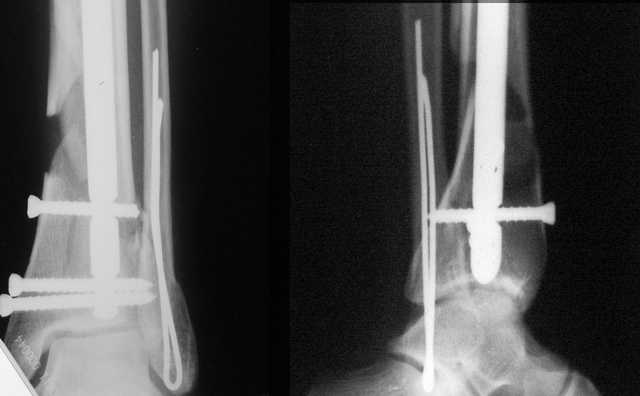

Да и нет! Зависит от перелома и способа остеосинтеза. А результат? (01)

А в данном случае - у нас был бы применен locked nail с еще меньшими дырочками на коже и с возможностью полной нагрузки немедленно после операции. Какие тут аргументы в пользу выбора пластины, а не интрамедуллярного гвоздя?

Аргументы: перелом достаточно низкий, трудно будет ввести 3-и блок. винта, а учитывая характер перелома на 2-х дистальных винтах я бы не рекомендовал немедленную полную нагрузку.